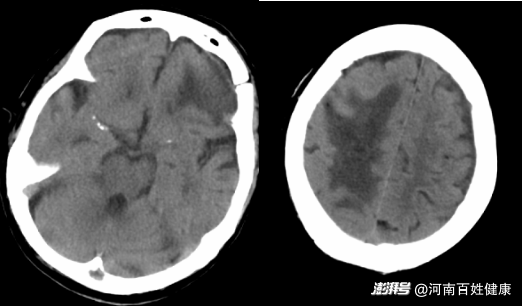

復(fù)查CT顯示

顱內(nèi)血腫基本吸收恢復(fù)較好

最終劉奶奶終于順利出院。如今她雖需借助輪椅活動,但語言清晰,能自主進食,左側(cè)肢體肌力已從0級恢復(fù)至3級?!罢鏇]想到86歲還能闖過這一關(guān),感謝醫(yī)生給了我媽第二次生命!”女兒在復(fù)查時感慨地說。